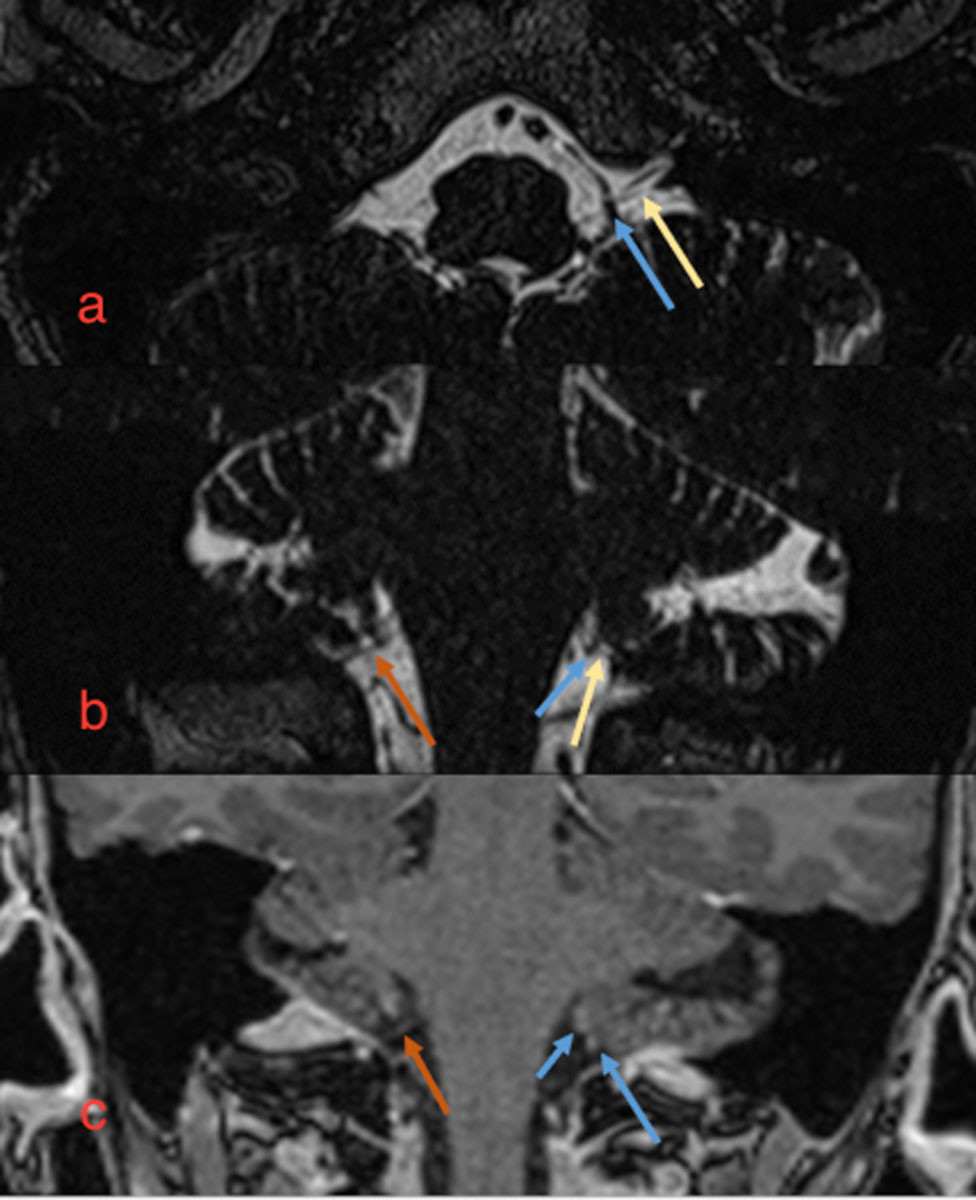

The maxillofacial surgeon suspected glossopharyngeal neuralgia and referred the patient for MRI with intravenous contrast to assess whether there were signs of nerve compression from surrounding blood vessels. MRI (3D T2 turbo spin echo and fat-suppressed T1 after intravenous contrast) of the head and skull base revealed asymmetry around the glossopharyngeal nerve. The course of the nerve on the right side was unremarkable, while several small vascular structures were observed along the nerve on the left side at the cerebellopontine angle. These were interpreted as small pial veins (Figure 1). No arteries were observed in relation to the nerve or signs of denervation of the stylopharyngeus. A small, round contrast uptake was noted at the dura in the foramen magnum on the left side, prompting further examination with CT angiography of pre- and intracerebral vessels to rule out an aneurysm. CT showed normal pre- and intracerebral arteries and no aneurysmal dilation of the posterior inferior cerebellar artery. Bilateral elongated styloid processes were observed.

The patient was recommended further titration of oxcarbazepine and an increase in the frequency of the cream mixture. Paracetamol 1 g × 4, etoricoxib 90 mg × 1 and amitriptyline 25 mg × 1 were also prescribed. The patient was referred for evaluation for decompression surgery due to glossopharyngeal neuralgia and was assessed by a neurosurgeon five months after the onset of symptoms. The condition was diagnosed as glossopharyngeal neuralgia with neuropathy. The clinical picture was deemed consistent with the MRI findings of arteries adjacent to the glossopharyngeal nerve on the left side, and the patient was referred for microvascular decompression surgery. Surgery took place six months after the onset of symptoms. Peroperatively, a large calibre vein was found along the entire course of the glossopharyngeal nerve on the left side, consistent with the MRI findings. The vein was separated and fixed away from the nerve. The postoperative period was uneventful, except for some nausea and dizziness. The patient was discharged to a local hospital after two days for further mobilisation. At a neurology check-up eleven weeks after surgery, the patient reported a significant improvement in pain, with shorter and less intense episodes than previously. One year after surgery, she experienced further improvement, and two years after surgery she continues to improve. She still sometimes experiences discomfort when exposed to the cold and when feeling tired. She underwent rehabilitation to normalise tongue and swallowing motor function, and her body weight has returned to normal (following a total weight loss of 10 kg up to the operation).